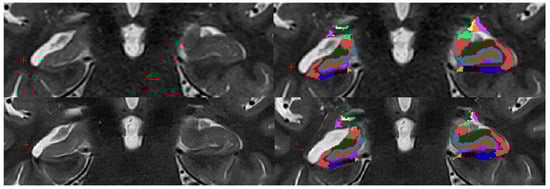

parasubiculum,

HATA,

fimbria,

hippacampal_fissure,

HP_tail,

presubiculum-head,

presubiculum-body,

subiculum-head,

subiculum-body,

CA1-head,

CA1-body,

CA3-head,

CA3-body,

CA4-head,

CA4-body,

GC-ML-DG-head,

GC-ML-DG-body,

molecular_layer_HP-head,

moleculcular_layer_HP-body.